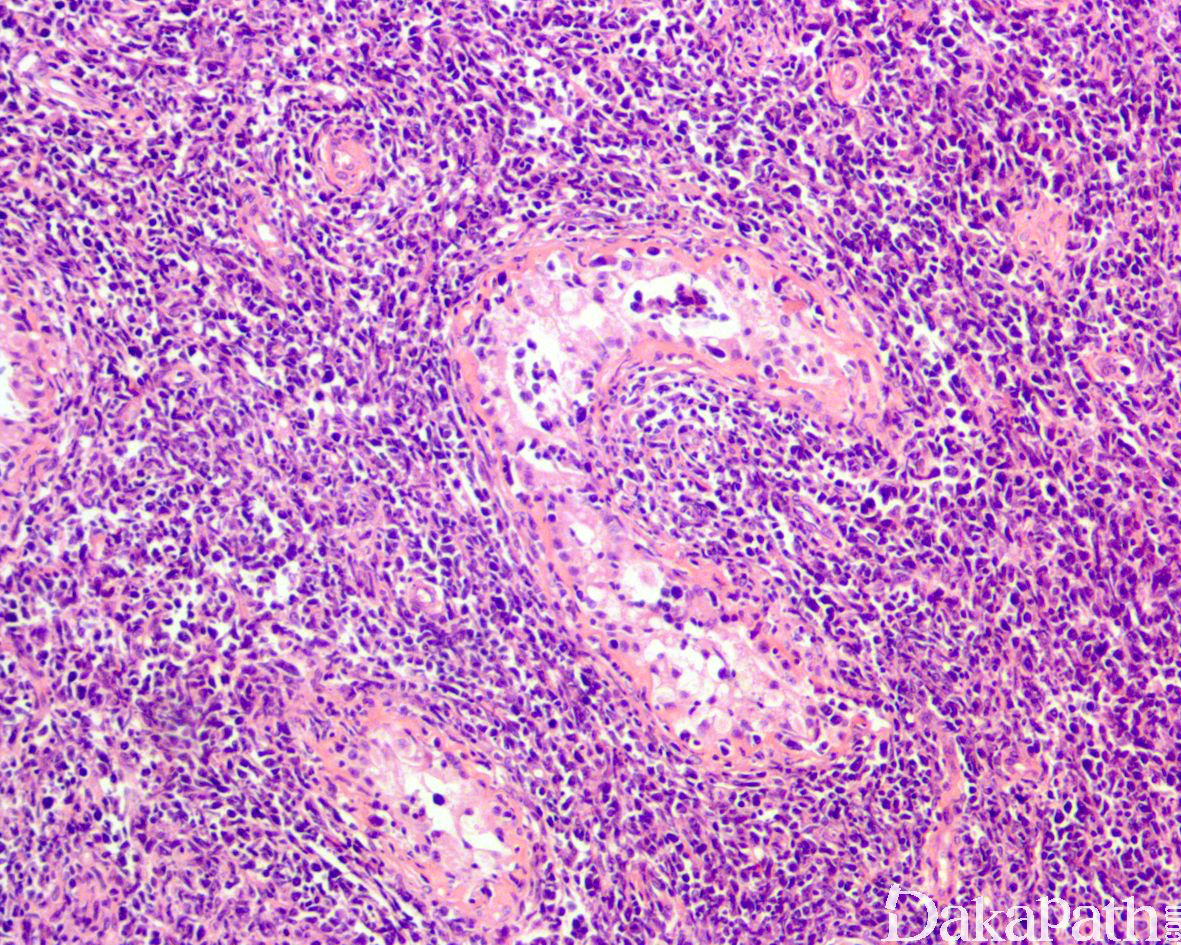

肿瘤由大的淋巴细胞构成,圆形或卵圆形,核形不规则,偶尔可见分叶核,核仁清楚,胞质稀少;

少数病例可伴硬化。

生殖细胞肿瘤:主要是精原细胞瘤,周围生精小管内可见原位生殖细胞肿瘤。免疫组化染色表达 OCT3/4,PLAP,SALL4 等,不表达 CD20 和 PAX5 可资鉴别。